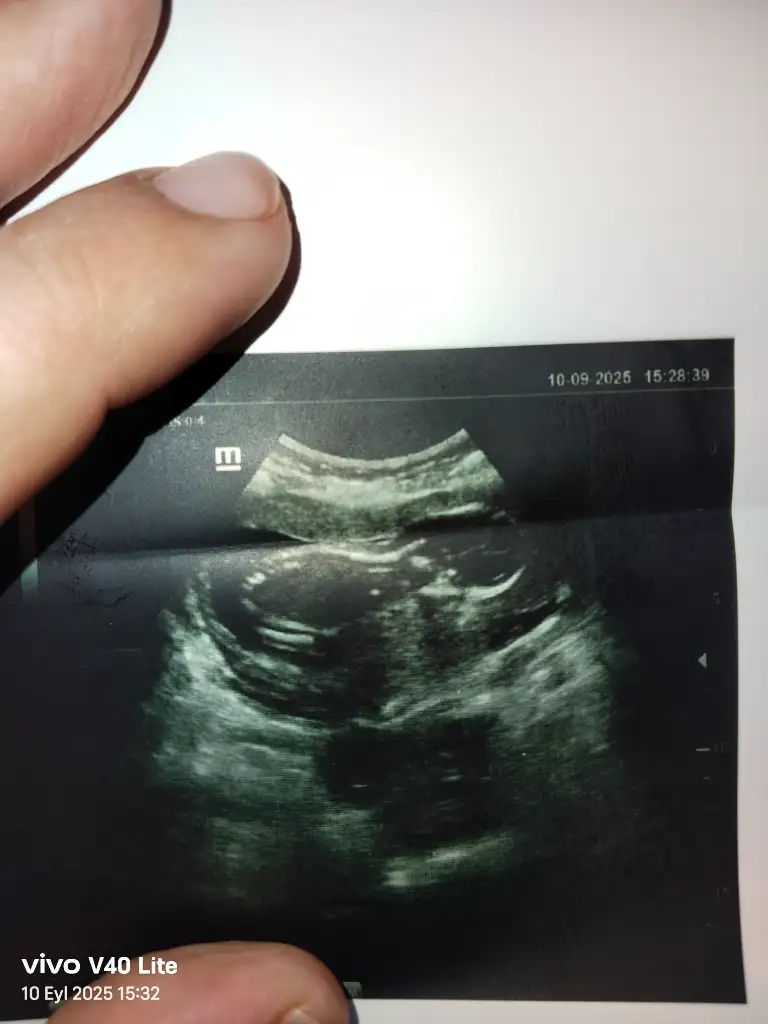

13+4 tahminde bulunabilir misiniz şimdiden teşekkür ederim.

• AB07C4B8-4141-4E2D-B914-B8AE22ADA7A7.webp

AB07C4B8-4141-4E2D-B914-B8AE22ADA7A7.webp

22,2 KB · Görüntüleme: 70